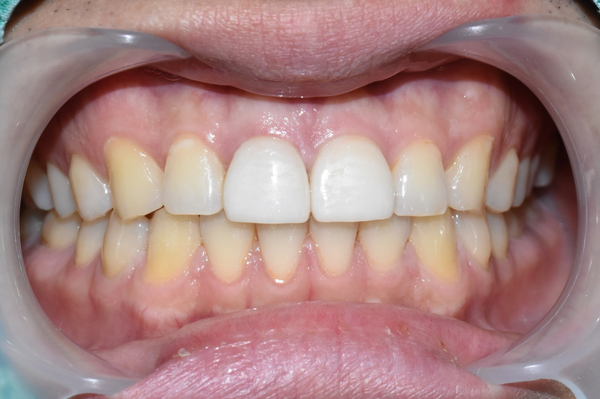

깨진 앞니, 변색된 앞니 2개 라미네이트 한 후 사진입니다.

변색을 가리기 위해 조금 불투명하게 제작되었습니다.

마스킹 과정을 철저하게 하고, 앞니 정중치 2개라서 기존 치아들보다 조금 더 하얗게 하면

전체적으로 치아들이 밝아보이는 효과도 있어서 조금더 하얗게 라미네이트를 하였습니다.

단, 변색이 없었더라면 마스킹이 특별히 안들어가도 되어서 치아의 투명감이 조금 더 자연스럽게 되었겠지만

변색때문에 마스킹이 들어가서 조금 불투명하게 제작된 점은 아쉬웠습니다.

그러나 입안에서 크게 부자연스럽지 않고 오히려 하얘서 웃었을 때 더 전반적으로 밝은 치아 이미지가 되었습니다.